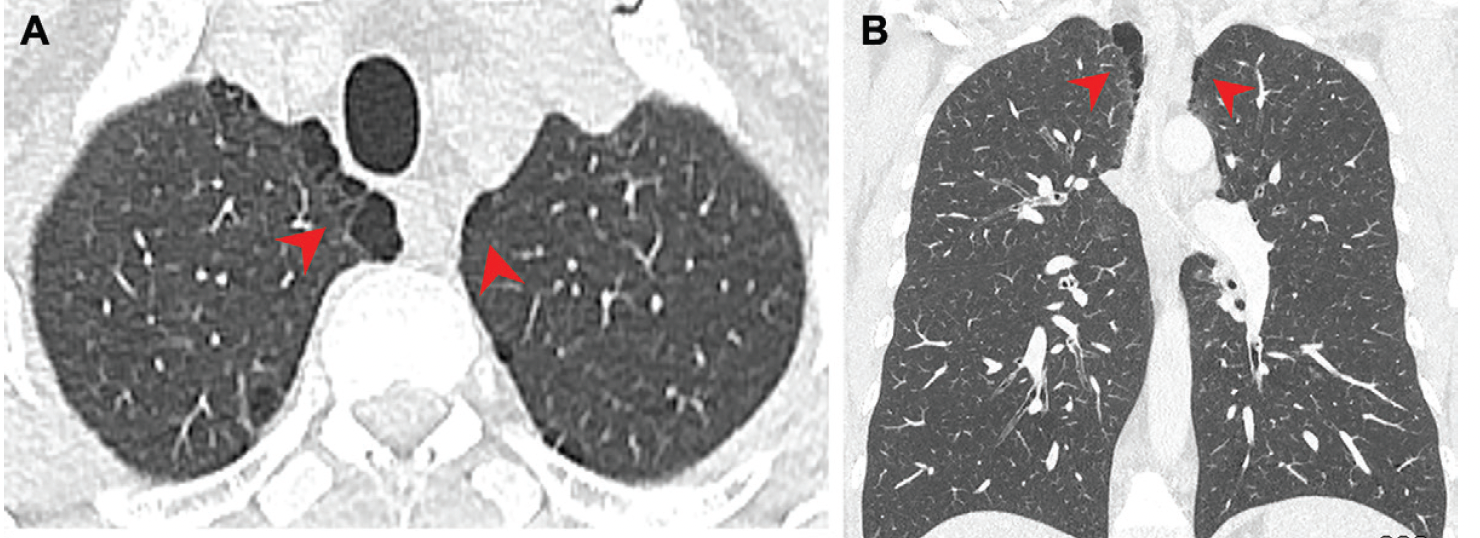

A new computed tomography study reveals that people who smoke marijuana may have a 70 percent higher risk of developing emphysema than non-smokers, and an age-matched subgroup analysis suggests marijuana use could be associated with a 26 percent higher risk of emphysema in comparison to tobacco-only smoking.